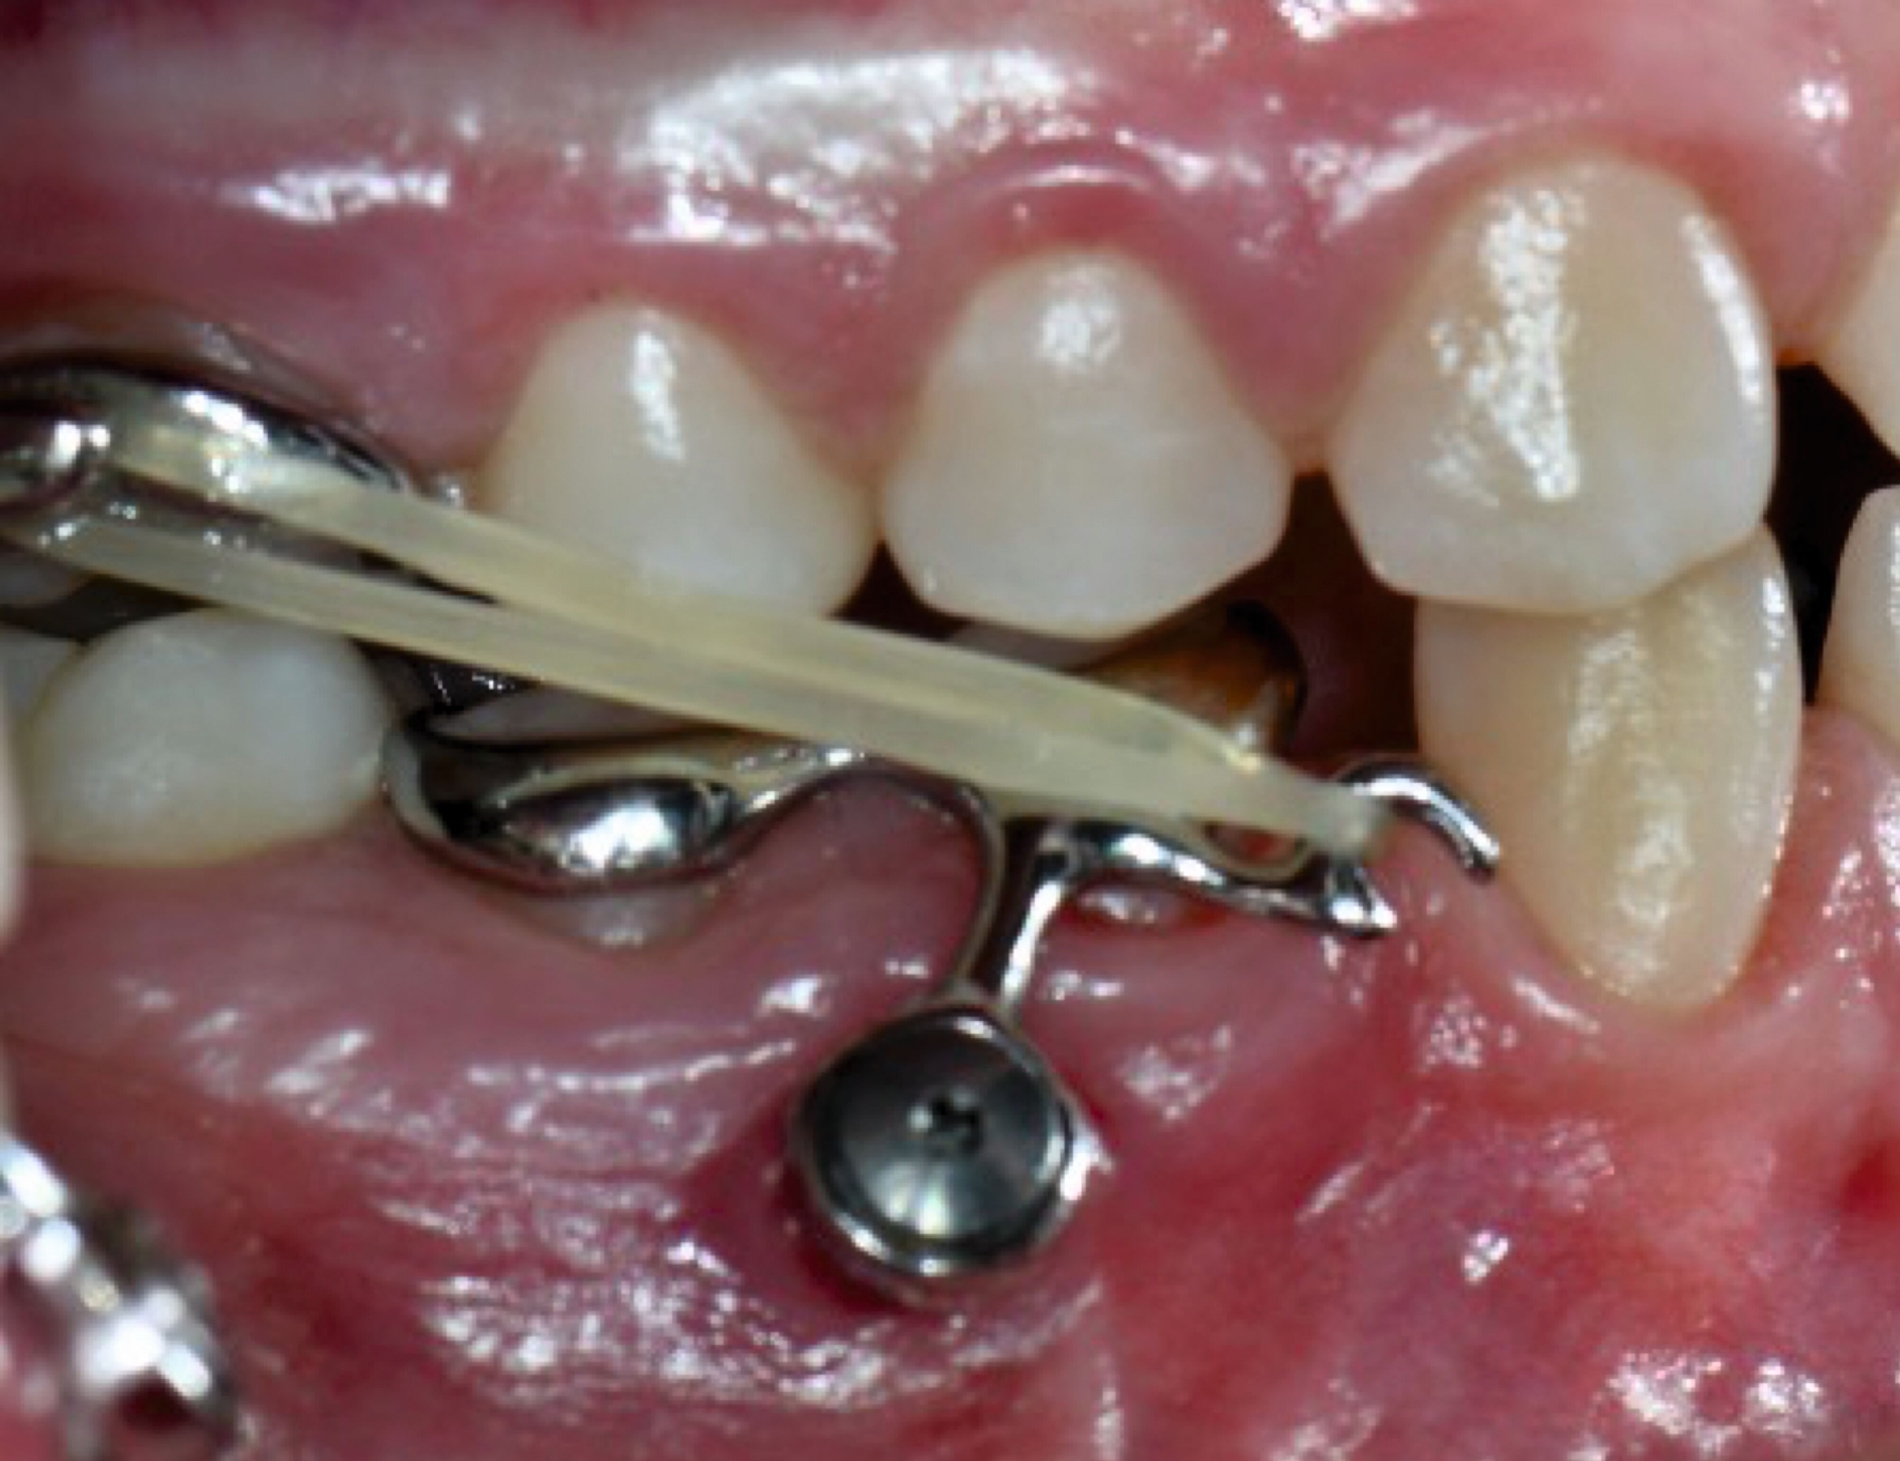

Anwendung findet der Metalldruck vor allem in der Herstellung skelettal verankerter Apparaturen, durch die reziproke Kräfte auf orthodontische Miniimplantate abgeleitet oder direkt skelettal aufgebracht werden können. Neben einer hohen Passgenauigkeit liegt der Vorteil vor allem in einer zielgerichteteren Therapie, die die anschließende oder zeitgleich durchgeführte Aligner- beziehungsweise Multibracket-Therapie verkürzt. Weiter können orthodontische Behandlungsaufgaben gelöst werden, die unter alleiniger Nutzung von Alignern beziehungsweise einer Multibracket-Apparatur deutlich limitiert wären. Beispiele beinhalten sogenannte „Mesialslider“ [Wilhelmy et al., 2022], „Distalslider“ [Graf et al., 2020] oder „Intrusionsapparaturen“.

Weiter erlauben hochindividuelle 3-D-gedruckte Designs die Therapie von skelettalen Fehlständen, beispielsweise in der Therapie defizitärer Maxillae [Pasqua et al., 2022; Bazargani et al., 2023; Ludwig et al., 2024] oder im Rahmen der nonoperativen oder postoperativen Prognathie-Behandlung [Hodecker et al., 2023]. Auch die Umsetzung skelettal verankerter Apparaturen mittels nichtmetallischer 3-D-Druckmaterialien findet in einzelnen Fällen Anwendung (Abbildung 3b). Zum Einbringen der Miniimplantate eignen sich sogenannte 3-D-gedruckte „Insertions-Guides“, die nach vorheriger digitaler Planung der Miniimplantat-Position, eine hochgenaue Insertion ermöglichen [Wilmes et al., 2022; Wilmes et al., 2022]. Die virtuelle Planung der Minischraubeninsertion ermöglicht eine sichere und nachvollziehbare Evaluation sämtlicher relevanter Gewebe, um die ohnehin geringen Risiken weiter zu minimieren. Zusätzlich kann man die Biomechanik der digital geplanten kieferorthopädischen Apparatur ideal koordinieren und – wenn man möchte – die Minischrauben und die Apparatur in einer Sitzung einsetzen.